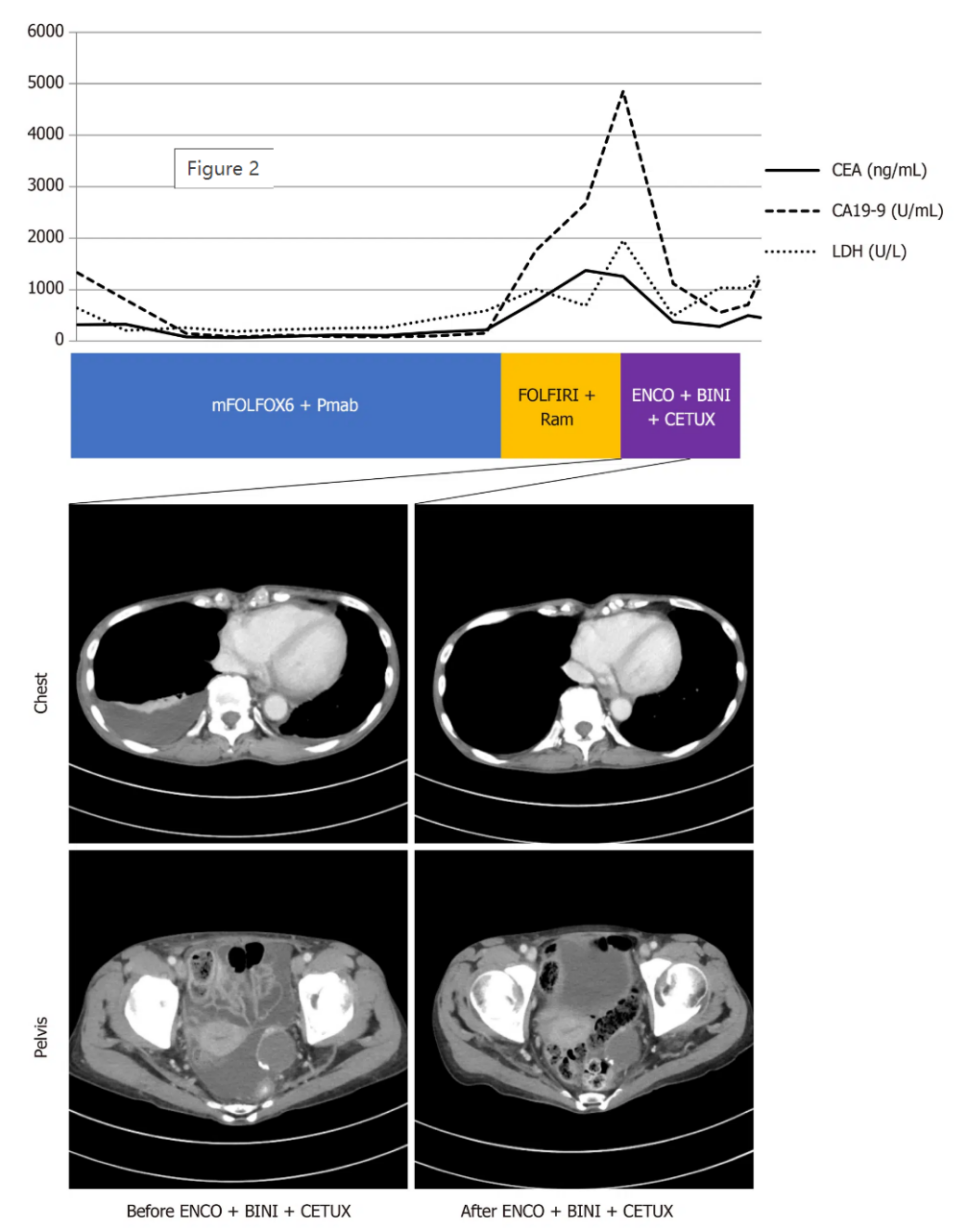

选择康奈非尼、binimetinib和西妥昔单抗联合用药作为三线化疗方案。治疗后,CEA、CA19-9和LDH水平下降(CEA 285.5 ng/mL,CA19-9 556.1 U/mL,LDH 491 U/L),同时胸腔积液和腹水有所改善(图2)。

图2. 三线治疗效果